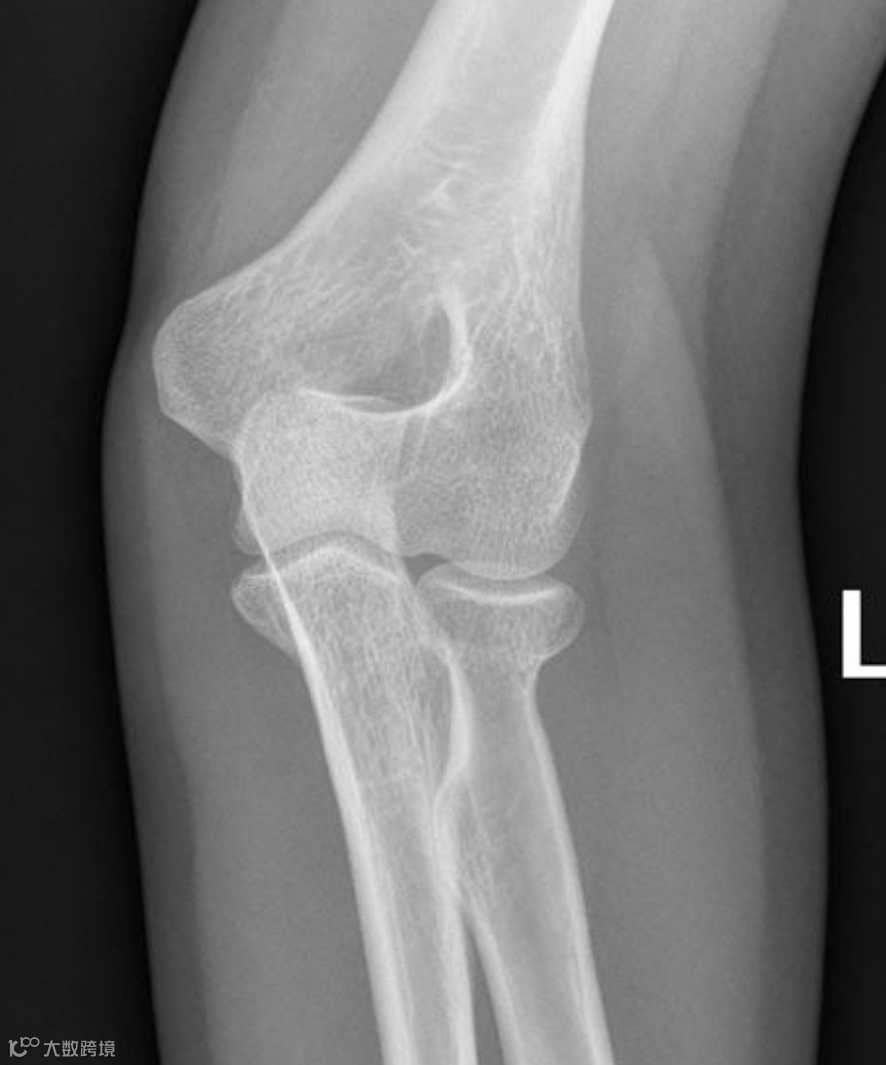

患者,女,30岁女子骑自行车摔倒,左肘着地,左肘关节正侧位X线示前、后脂肪垫征阳性(八字征),桡骨头外侧轮廓略显模糊,但未见明缺的骨折线。

同一患者,1周后复查,桡骨颈部可见一条细而模糊的硬化线,证实为桡骨颈骨折。